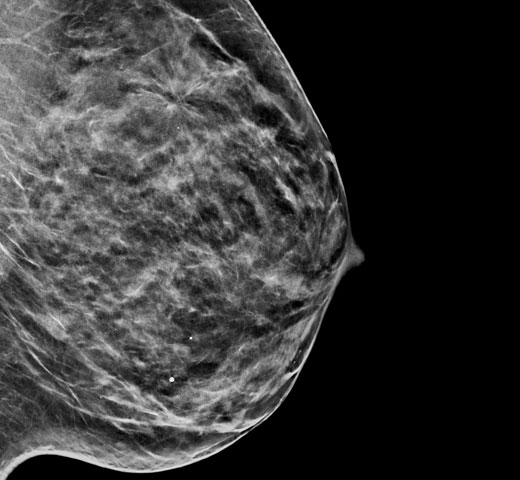

A mamografia com contraste (CEM, do inglês «Contrast Enhanced Mammography»), o sistema de imagem da mama que utiliza contraste de iodo para realçar as áreas com maior fluxo sanguíneo na mama pode ajudar a destacar lesões suspeitas. O software I-View consegue combinar a potência da CEM com as imagens 2D e de tomossíntese, tudo com apenas uma compressão, fornecendo um sistema de imagem anatómico e funcional num único exame.1